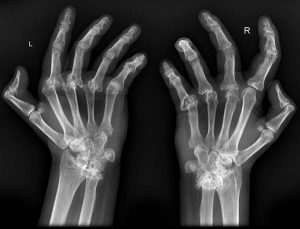

ARTROSIS DE MANO. FISIOTERAPIA Y REHABILITACIÓN EN ARTRITIS REUMATOIDE.

La artritis reumatoide es una enfermedad autoinmune articular crónica, progresiva y con afectación sistémica. Su etiología es desconocida, normalmente con antecedentes familiares. Predomina en el sexo [...]